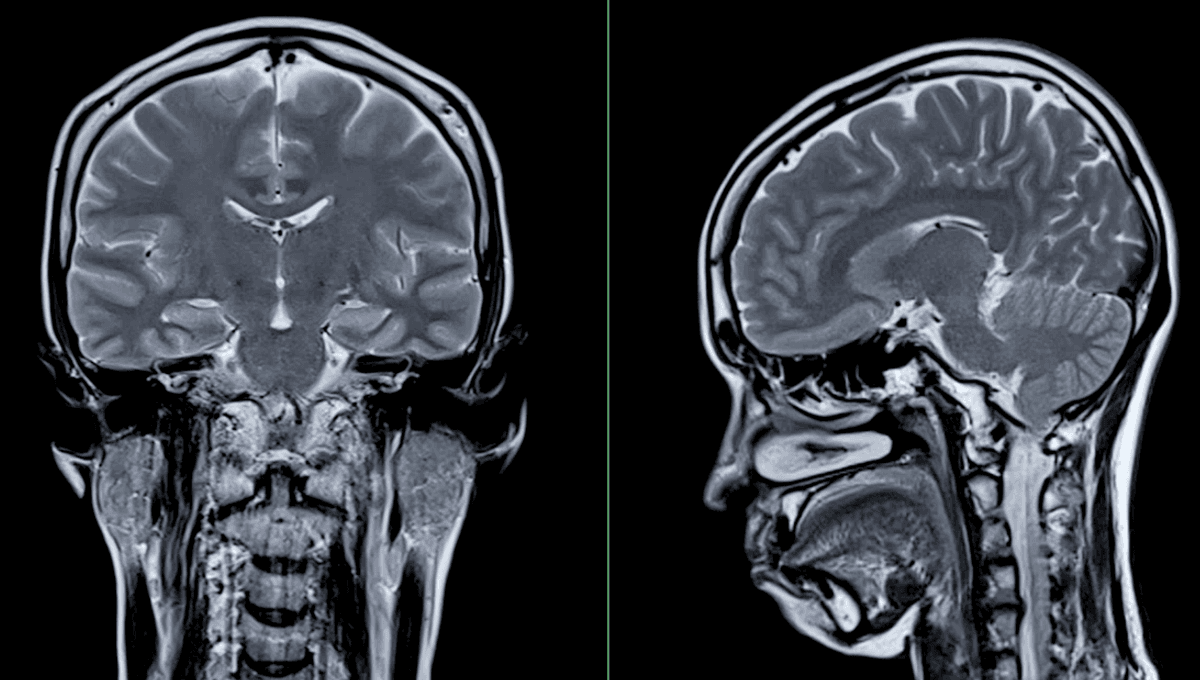

People Are Sharing Scans Of Gaps In Their Brains On Reddit

The remarkable science of brain plasticity.